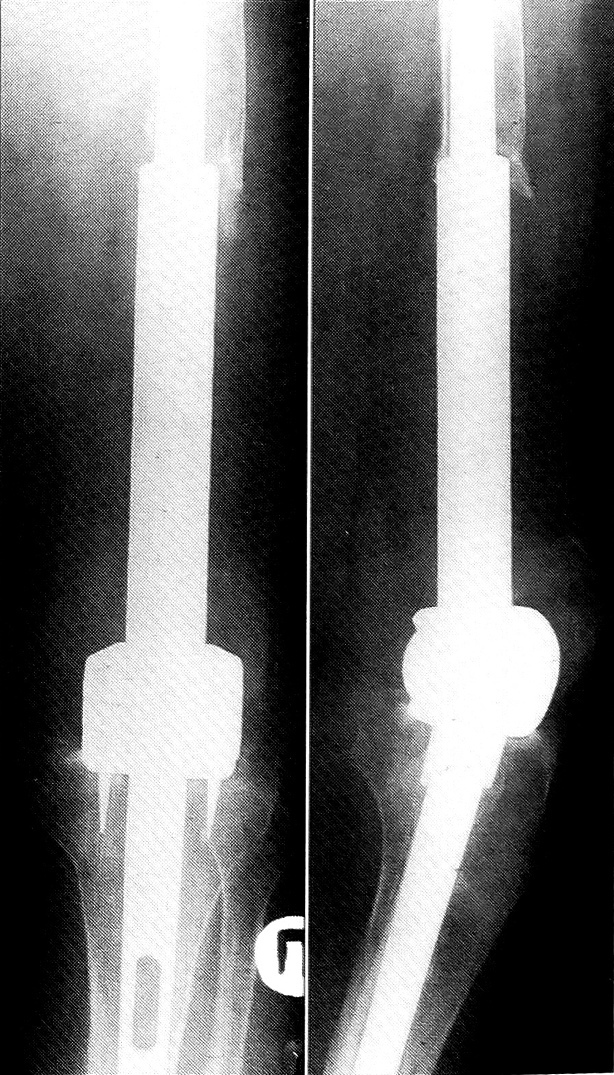

Клинически выявляются признаки воспалительного процесса: кожа нижней трети бедра гиперемирована, горячая на ощупь, ткани отечны, пальпация болезненна, активные и пассивные движения в коленном суставе отсутствуют. На рентгенограммах (рис. 1): нижняя треть бедренной кости резецирована и замещена эндопротезом с укреплением его ножек в бедренной и большеберцовой костях цементом. Ось эндопротеза несколько отклонена кнутри. В области дистального конца оставшейся части бедренной кости определяются слоистые неконсолидированные и бахромчатые периостальные наслоения, более выраженные, чем на снимках 4-месячной давности. В динамике отмечается также разрежение костной структуры в области опила бедренной кости, костные балки на этом фоне четко не прослеживаются. Заключение: состояние после резекции дистального суставного конца бедренной кости с эндопротезированием; рентгенологическая картина может соответствовать воспалительным изменениям в области опила бедренной кости, однако нельзя полностью исключить рецидив опухолевого процесса.

Рис. 1. Рентгенограммы больного А. при поступлении: состояние после резекции дистального суставного конца бедренной кости и имплантации эндопротеза Сиваша. Определяются признаки нагноения и расшатывания эндопротеза.